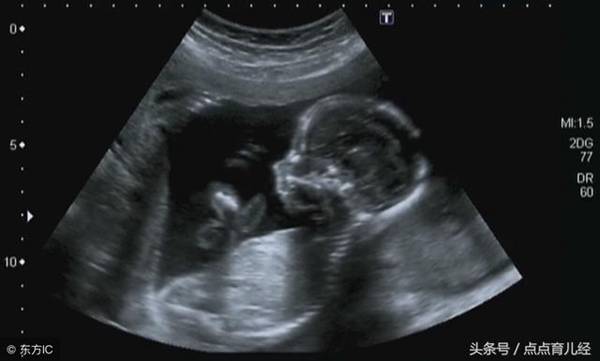

4、四维彩超比三维彩超更优势的地方是它可以呈现动态的图像,你不仅可以直观的看到宝宝的样貌,还可以看到某一瞬间宝宝活动的情景,吃手、吐羊水、蹬腿、捂脸这些动作可以通过四维彩超表现出来。